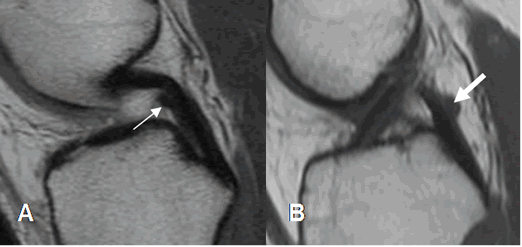

Fig 19. Ligamentos meniscofemorales normales.

A: RM coronal en T1 y B: RM coronal en STIR. Ligamento menisco femoral posterior (Flecha delgada), en relación con el LCP (Flecha gruesa). Menisco externo (Punta de flecha).

Los ligamentos colaterales unen el fémur distal, con la tibia y el peroné proximal. (Fig 20).

Fig 20. Ligamentos colaterales normales.

A y B: RM coronal en T1. LCL en A y LCM en B.